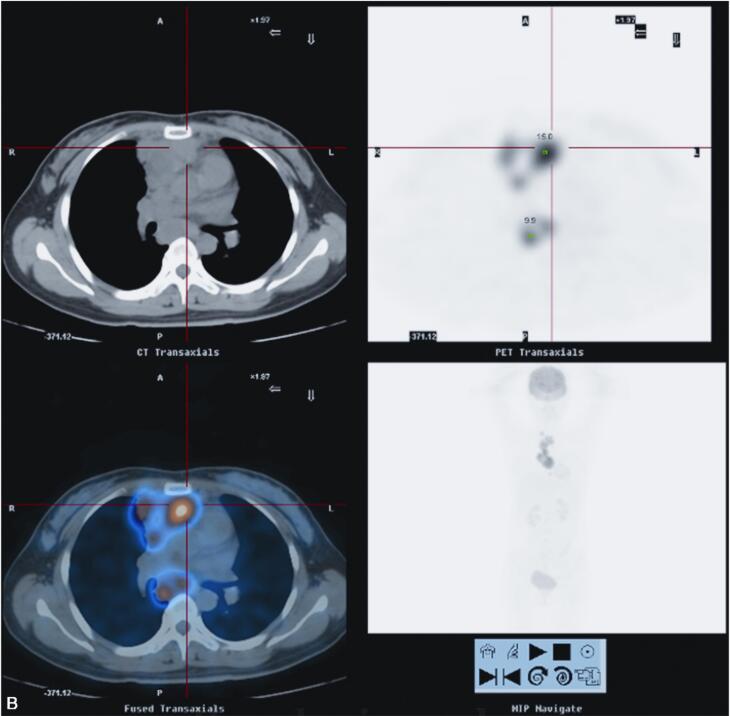

2010年5月10日于我院18F-FDG PET/CT检查:纵隔内及右肺上叶前段病变,代谢异常升高,考虑慢性感染性疾病可能性大(结核肉芽肿?),请结合临床,进一步完善结核相关检查,必要时纵隔镜活检以除外恶性病变(图2)。

图2 PET/CT示右肺上叶前段纵隔旁见高密度实变影,内见充气支气管影,FDG代谢放射性分布异常浓聚(SUVmax=12.4)。前纵隔内见软组织密度肿块影,最大截面积约为5.2cm×3.0cm,其内密度不均,见低密度坏死区,实质区FDG代谢放射性分布异常浓聚(SUVmax=15.0),邻近心包;右锁骨上、前上纵隔、主肺动脉窗,气管叉下(其内见钙化灶)及心包右旁见肿大淋巴结影,部分融合趋势,FDG代谢放射性分布异常浓聚